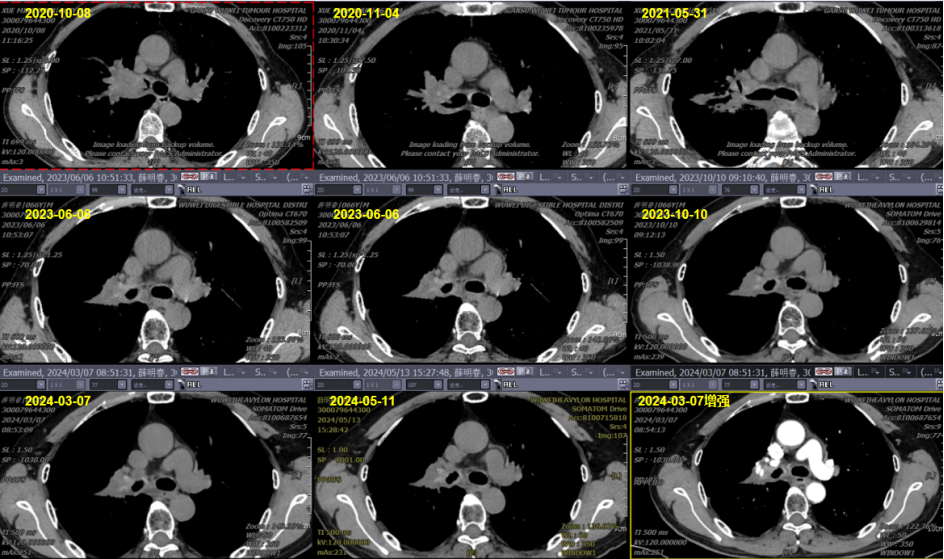

临床安全性数据: 基于上述物理和生物学优势,重(碳)离子治疗后放射性损伤多为1~2级。文献报道,光子立体定向体部放疗的严重肺损伤(≥3级)发生率范围为0-28%,而重(碳)离子治疗的所有报道均显示该发生率低于8%。本组患者治疗期间及后续随访中,3级及以上急性或晚期不良反应非常低且可控,表明重(碳)离子治疗非小细胞肺癌安全可行,患者耐受性良好。病例插图病例一:薛某某,63岁,右肺中央型鳞癌,cT2N3M0 分期,IIIB 2020年10月重(碳)离子治疗,随访至今,状况良好。

病例一:薛某某,63岁,右肺中央型鳞癌,cT2N3M0 分期,IIIB 2020年10月重(碳)离子治疗,随访至今,状况良好

该患者治疗前后的长期随访,右肺中央型病变完全消失

病例提供医生:王馨 科室:放疗中心一科(国际一部)